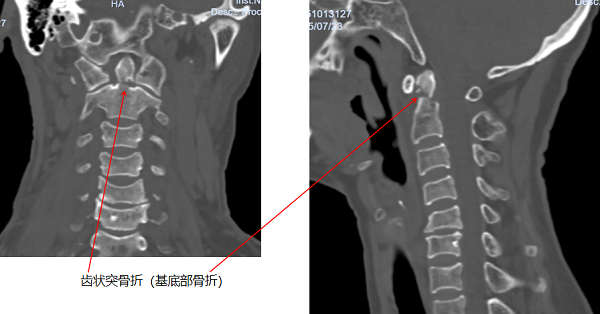

据悉,老奶奶在田间劳作时,不慎从2米高的田埂跌落至沟中,被救护车送至当地医院后,CT检查提示颈椎骨折,随即紧急转入玉溪市人民医院。进一步检查中发现,老人伤情复杂,不仅存在颈椎齿状突骨折、胸腰椎多发骨折、双侧腕关节骨折,还合并头部硬膜外血肿,病情危急。

图片1

骨外一科值班医生第一时间启动多学科会诊机制,邀请神经外科、骨外三科专家共同评估病情,围绕患者头部及腕关节外伤制定紧急处理方案,始终坚守“生命第一”的救治原则,快速稳住老人生命体征。待病情平稳后,科室结合骨外三科意见,决定对愈合难度极高的Anderson II型齿状突骨折、第一腰椎骨折实施手术治疗,其余部位采取保守治疗。